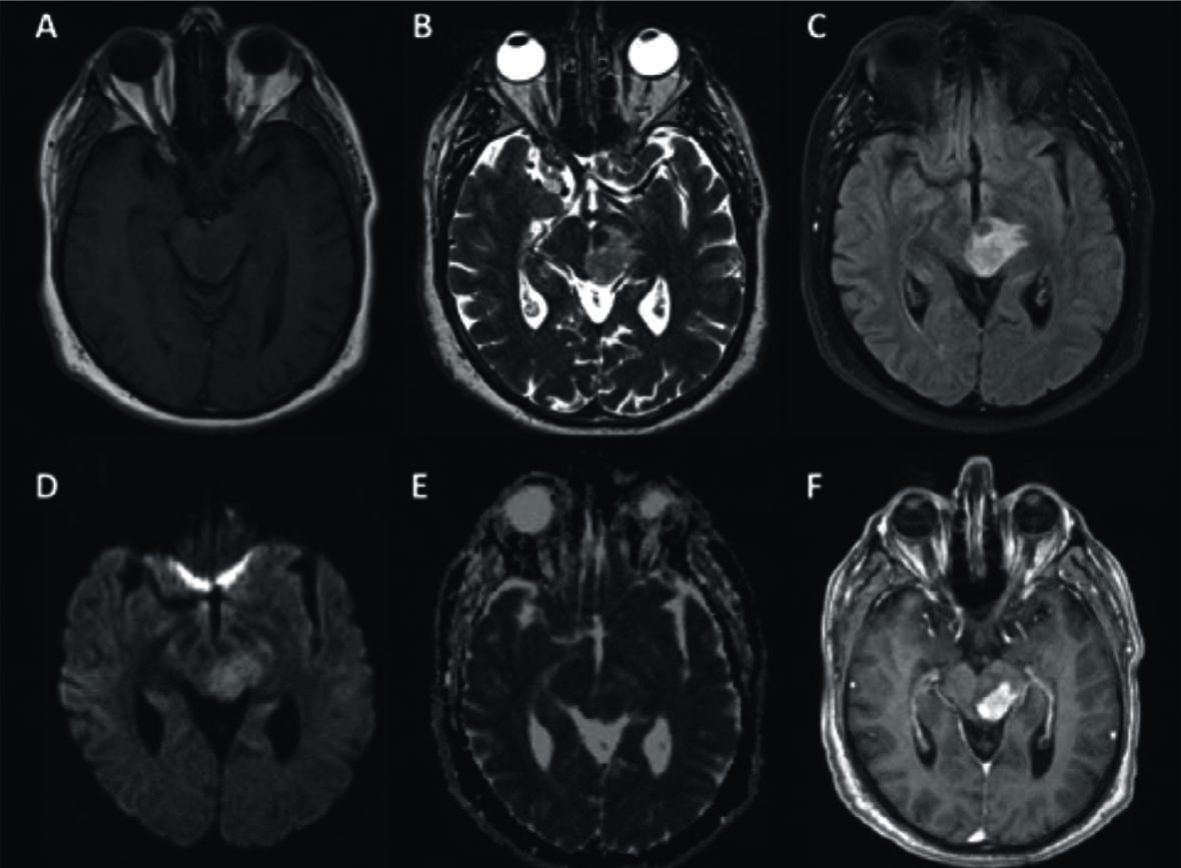

Figura 2

LPSN con lesión única de tronco encefálico (mesencéfalo).

Se identifica la lesión hipointensa en T1 (A) en el mesencéfalo, hiperintensa en T2 y FLAIR (B y C) con escaso edema, y fenómeno de restricción en difusión (D) y ADC (E). Con el medio de contraste (F) se observa el clásico patrón de realce intenso con borde irregulares.

Figura 3

LPSN con compromiso multifocal supra e infra-tentorial.

Paciente de 53 años con cefaleas progresivas y diagnóstico de LPSN multifocal. Se identifican focos supra-tentoriales hipointensos en T2 (A) con importante edema asociado en FLAIR y una lesión de fosa posterior (B y C). En T1 son lesiones de baja señal (D) presentando con gadolinio un intenso realce y con bordes irregulares (E y F). A nivel infra-tentorial la lesión es cerebelosa izquierda (B y F).